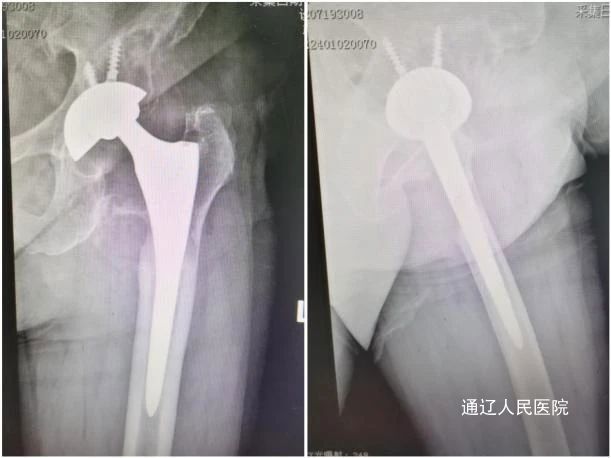

术后X线检查